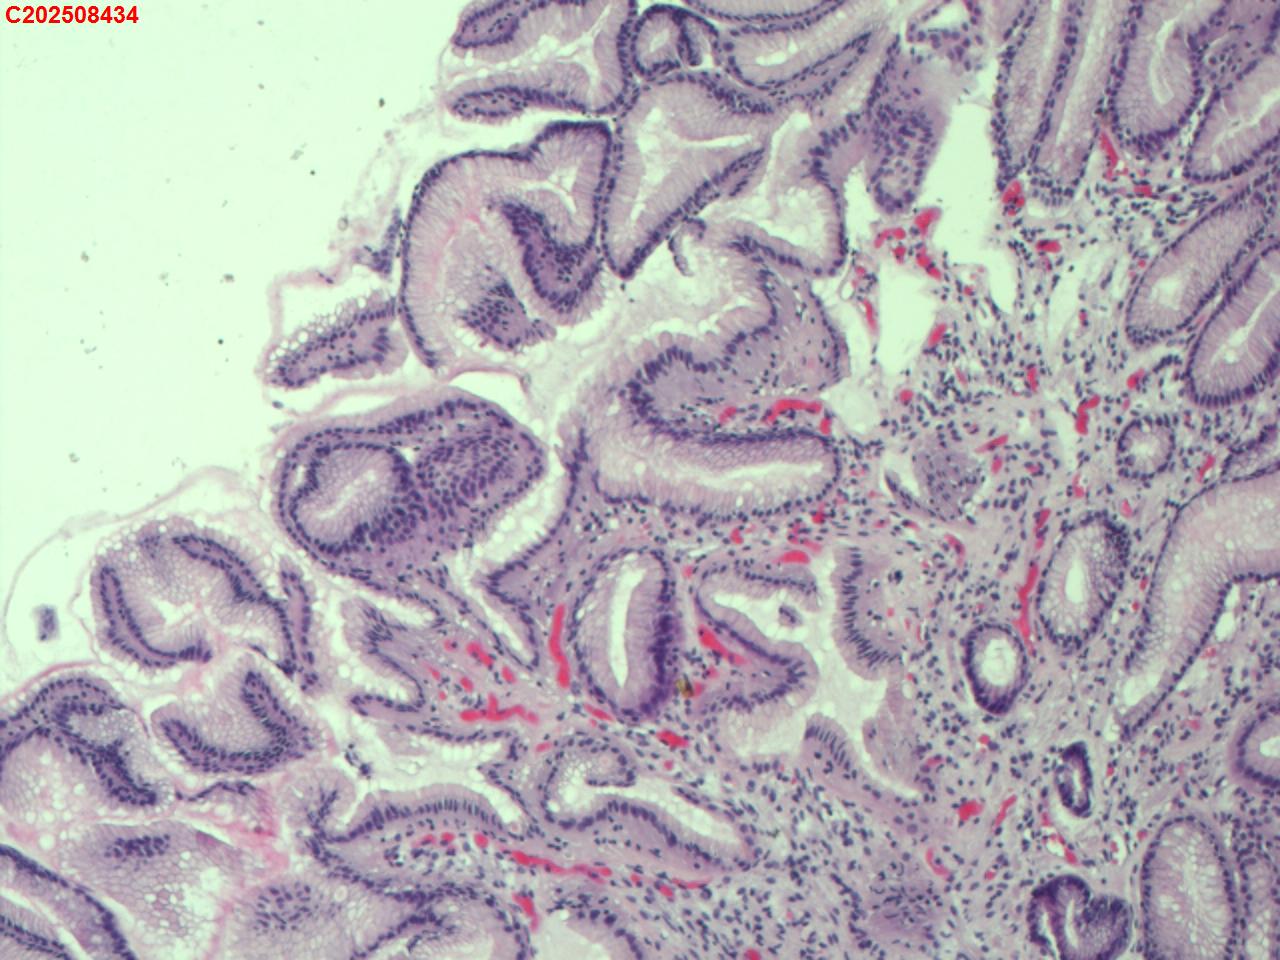

胃体粘膜

性别

男

年龄

65岁

临床诊断

胃体息肉

一般病史

肝病病史

标本名称

大体所见

胃体可见直径2-3mm的息肉样隆起。

增生性息肉。

符合增生性息肉。